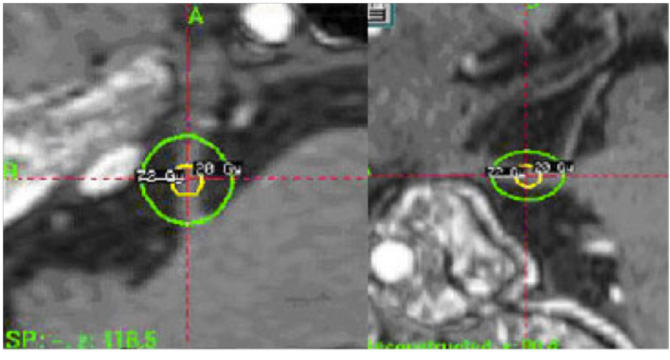

圧迫された神経を示すMRI